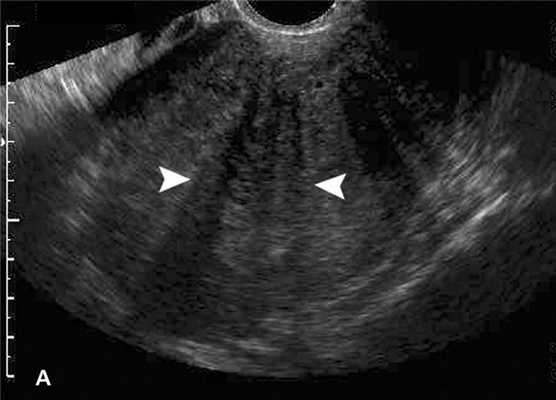

Признаки аденомиоза матки на УЗИ характеризуются заметными отклонениями от общепринятых физиологических норм. Патология лучше всего визуализируется в начале второго цикла лютеиновой фазы, когда функции эндометрия активны больше всего.

Характерные эхо-признаки аденомиоза на УЗИ:

неоднородность тканей миометрия;

смазанные границы между ростковым и мышечным слоями;

округлая форма органа;

асимметрия в толщине стенок;

наличие спиральных сосудов эндометрия в миометрии;

отклонение от норм по длине, ширине, массе более чем на 10%;

очаги уплотнений, пустот более 2 мм внутри мышечного слоя.

Аденомиоз на УЗИ проявляется изменениями плотности тканей матки, а также наличием областей с гипоэхогенностью, гиперэхогенностью, гетероэхогенностью. Также во время ультразвукового исследования выявляются патологические пятна с нарушенной плотностью размером 1 - 50 мм.

Ультразвуковое исследование органов малого таза - доступный, результативный, безопасный, безболезненный метод диагностики, который при подозрении на аденомиоз рекомендуется выполнять в динамике на 8 - 10 и на 20 - 24 дни цикла. Процедура поможет определить степень патологических изменений в структуре репродуктивного органа. На 1 стадии аденомиоза матка на УЗИ немного увеличена в размерах, а в проекции стенок определяются небольшие кистозные образования в диаметре до 2 - 3 мм. Наличие кистозных включений делает структуру миометрия неоднородной, ее эхогенность слегка повышена.

На 2 - 3 стадии клетки эндометрия распространяются на мышечную ткань по направлению к серозному слою, что указывает на диффузную форму патологии, которой характерны такие признаки:

неоднородная структура органа;

неравномерность толщины стенок;

линейная исчерченность срединного М-эхо, размытость его контуров;

увеличение органа в размерах.